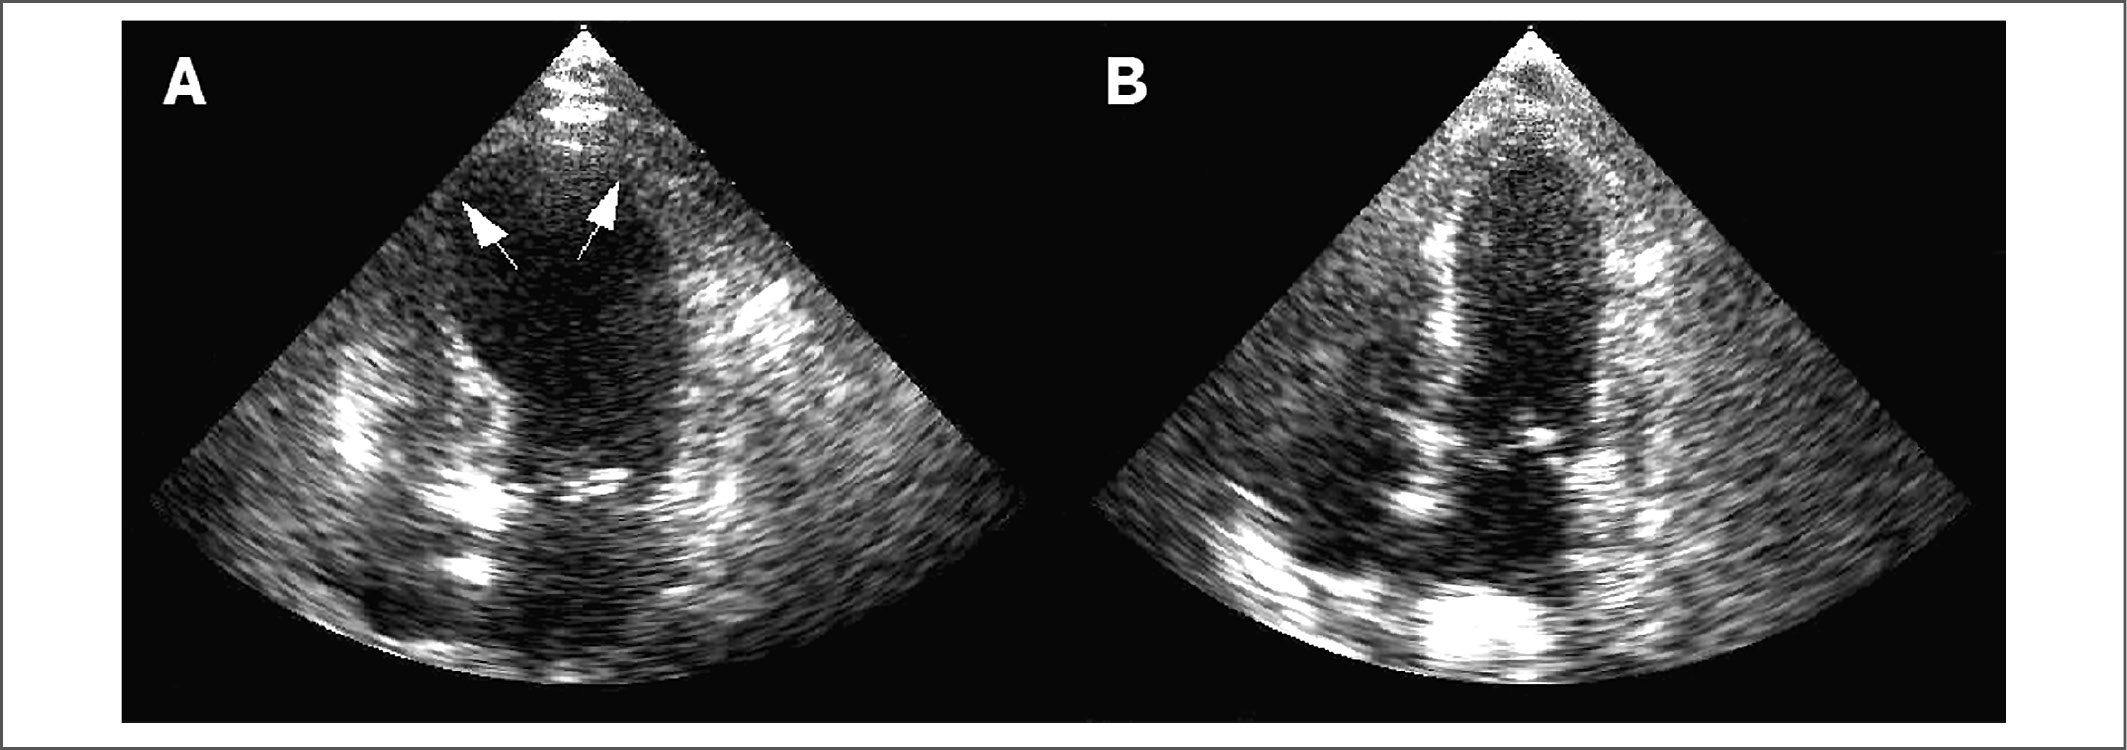

Рис. 2. Результаты ЭхоКГ. А – баллонирование верхушки в остром периоде кардиомиопатии такоцубо, B – исчезновение патологических изменений в процессе наблюдения.

Fig. 2. Echo results. A – punctuation of the apex in the acute period of takotsubo cardiomyopathy, B – elimination of pathological changes during observation.

Наиболее специфичные изменения выявляются при ЭхоКГ и контрастной вентрикулографии (см. рис. 1, 2). Трансторакальную ЭхоКГ считают методом выбора для определения варианта поражения миокарда и сократительной способности ЛЖ при СТ. Характерны а- или дискинез верхушки и средней части ЛЖ с гиперконтрактильностью основания и обструкцией выходного тракта ЛЖ (taco-tsubo). Общая систолическая функция снижается, иногда значимо (до 20%).

По мнению отечественных исследователей, ЭхоКГ играет ведущую роль в диагностике СТ и позволяет отразить регресс нарушения функций сердца на основании динамики локальной сократимости и оценки локальной продольной деформации миокарда на базе технологии выявления пятен (speckle tracking) при двухмерном изображении [4]. Однако, невзирая на наличие различных форм СТ, характерно одинаковое восстановление функционального состояния ЛЖ в исходе заболевания [3, 4, 7].